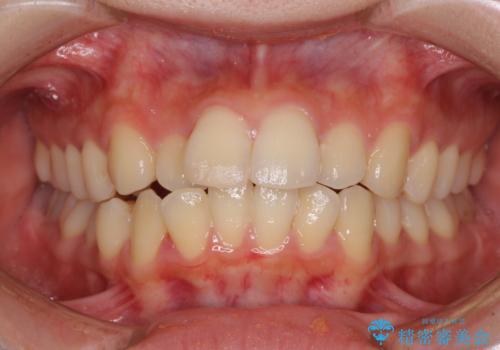

- 口元の閉じにくさを気にして来院された患者様です。

上下ともに歯列が前方に突出していたため、上下左右の第一小臼歯4本を抜去し、ワイヤー装置による矯正治療を行うこととしました。

舌の突出癖による影響もあったため、舌のトレーニングを並行して実施しました。